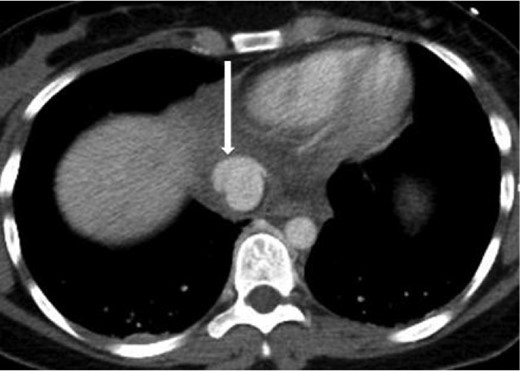

A 20-year-old female was the restrained driver of a vehicle traveling ∼45 miles per hour when her vehicle crashed into a city bus. She was extricated on scene by emergency responders and brought to the trauma bay alert, oriented and in stable condition complaining of pain on deep inspiration as well as left leg pain. She denied any abdominal pain or light-headedness. Vital signs on arrival were heart rate of 115 bpm, respiratory rate of 20 breaths per minute and blood pressure of 101/76 mmHg; her Glasgow coma scale was 15. The initial chest radiograph showed a small, right-sided pneumothorax and pulmonary contusions. Two radiographic views of the left leg revealed comminuted, mildly displaced tibia and fibula fractures. Computed tomography (CT) scans of the brain and neck were unremarkable. A contrast-enhanced chest CT scan demonstrated non-displaced right lateral second and third rib fractures, right upper lobe pulmonary contusions with laceration and a small pneumothorax, partially visualized grade 5 liver laceration with active contrast extravasation, and an acute, traumatic supradiaphragmatic IVC injury with an associated moderate hematoma and contrast extravasation that appeared to be contained, as seen in Figs 1 and 2. In view of incompletely imaged critical findings of the upper abdomen and continued hemodynamic stability of the patient, a dedicated abdomen and pelvis CT scan, seen in Figs 3–5, was performed 20 min later, which showed a stable 1.3 cm pseudoaneurysm of the supradiaphragmatic IVC without extension into the pericardium, stable moderate pericaval hematoma surrounding the injury, stable grade 5 liver laceration and a trace amount of fluid in the peritoneal cavity. A liver transplant surgeon and a cardiovascular surgeon were consulted due to the presence of acute traumatic suprahepatic IVC pseudoaneurysm.

Axial contrast-enhanced CT of the abdomen performed 30 min after the initial CT of the chest showing persistence of the abnormal contour of the supradiaphragmatic IVC with contrast extravasation confined laterally and ventrally (arrow), nonexpanding pericaval hematoma.